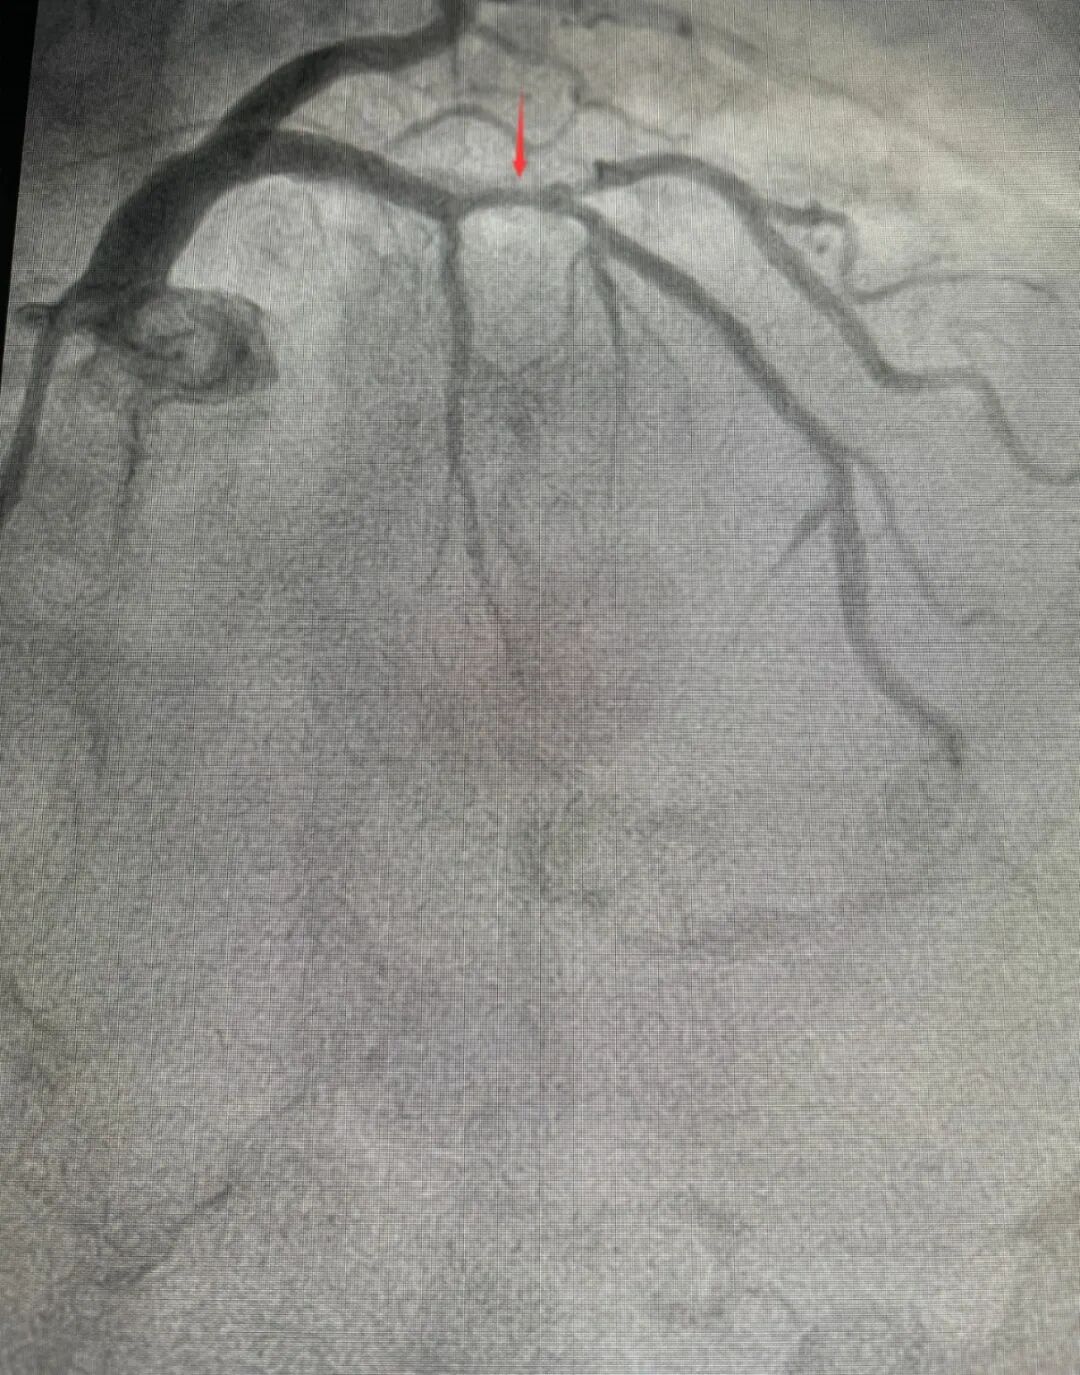

在十二病区(心血管内科)经冠脉造影检查,接诊医生发现张大妈左前降支近中段存在严重弥漫钙化病变,最狭窄处达90%。

这是一个不小的问题。心血管内科团队决定为其实施经皮冠状动脉介入治疗(PCI)治疗,这是一种经心导管技术疏通狭窄甚至闭塞的冠状动脉管腔,从而改善心肌的血流灌注的治疗方法。

术中,医生发现由于张大妈动脉钙化严重,血管通道狭窄,普通预扩张球囊与超声导管均无法穿越病变。但好在术前做了充足准备,面对这一情况团队立即采用备选方案——冠状动脉旋磨术。手术成功开通被钙化斑块堵塞的血管,术后张大妈症状明显缓解,恢复良好。